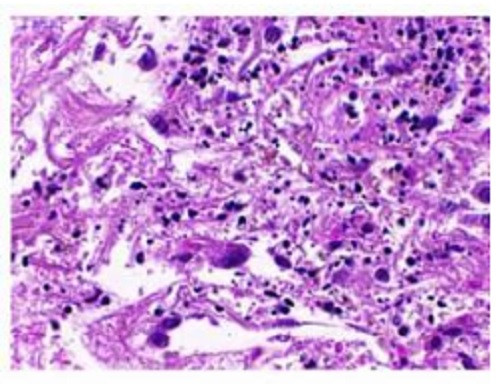

Thử nghiệm sử dụng thuốc trên mẫu ung thư phổi cho thấy các tế bào ung thư đã chết. Ảnh: weizmann.ac.il

Nghiên cứu mới do nhóm nhà khoa học tại Viện Khoa học Weizmann (WIS) của Israel cùng các đồng nghiệp tại Viện Công nghệ Massachusetts và Đại học Harvard (Mỹ) phát triển đã được đăng tải trên tạp chí Nature Communications. Phương pháp này dựa trên việc gán điểm số cho các hoạt động truyền thông tin nội bộ của các tế bào khối u ác tính. Đây là những chuỗi tín hiệu sinh hóa truyền tải các thông điệp quan trọng của tế bào, chẳng hạn như liệu một tế bào nên phân chia hay phát triển, hay theo cách thay đổi phương thức chuyển hóa.

Cụ thể, thông qua việc sử dụng một công cụ hiện đại và bộ dữ liệu khổng lồ, nhóm nghiên cứu đã gán cho từng chuỗi phản ứng hóa sinh một điểm hoạt động, bao gồm mức độ biểu hiện gene, cấu trúc chuỗi phản ứng hóa sinh, sự tương tác giữa các gene trong chuỗi phản ứng đó... Kế đến, họ phân tích mối tương quan giữa các điểm số này với bộ cơ sở dữ liệu chứa thông tin về độ nhạy của các tế bào ung thư khác nhau trước gần 500 loại thuốc chống ung thư khác nhau. Kết quả phân tích chỉ ra rằng điểm số hoạt động của một vài trong số các chuỗi phản ứng sinh hóa cho phép họ có thể dự đoán loại thuốc nào có tác dụng điều trị với một khối u ác tính cụ thể.

Thông qua phương thức trên, nhóm nhà khoa học đã tạo ra một hồ sơ u ác tính, giúp các bác sĩ có cơ sở để tư vấn loại thuốc nào tốt nhất giúp triệt tiêu khối u ác tính của từng bệnh nhân cụ thể. Hướng đi mới này được kỳ vọng có thể giúp các nhà nghiên cứu xác định các điểm yếu của nhiều khối u để từ đó có thể phát triển các loại thuốc điều trị phù hợp.